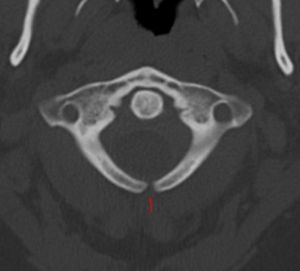

Unfused arch of C1 at CT.

There are various defects associated with vertebral development. Scoliosis will result in improper fusion of the vertebrae. In Klippel-Feil anomaly patients have two or more cervical vertebrae that are fused together, along with other associated birth defects. One of the most serious defects is failure of the vertebral arches to fuse. This results in a condition called spina bifida. There are several variations of spina bifida that reflect the severity of the defect.